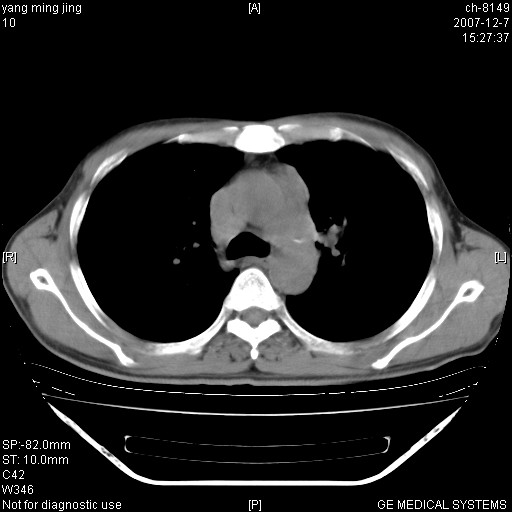

以下是引用zsl6918在2007-12-7 22:22:00的发言:[br]左肺上叶中心性肺癌并肺内及纵隔淋巴结转移,肝内转移。小细胞肺癌可能性大。

以下是引用狙击手在2007-12-8 11:03:00的发言:[br]考虑:左肺上叶中心性肺癌并肺内及纵隔淋巴结转移,肝内转移。